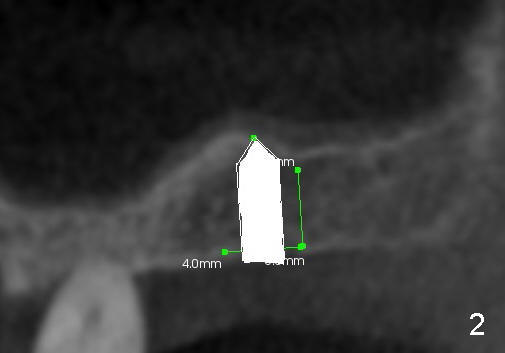

Fig.1 shows the sagittal section of the upper right posterior quadrant (3: #3 palatal root, 2: edentulous area to receive implant; S: sinus). The bone height is 5.8 mm. If the trephine bur with 4 mm outer diameter) does not engage into the bone easily, a 2.0 mm pilot drill is used to create initial osteotomy short of sinus floor (~4 mm deep). Osteotomy is increased by sequentially using 2.5, 3.0, 3.5 and 4.0 mm reamers (Fig.3). Bone shaving is saved. The last 1-2 mm of osteotomy (i.e., sinus floor) is prepared using 4 mm trephine bur (Fig.4 red lines). A flat end osteotome (4 mm in diameter, Bicon comprehensive kit) or tap is used to push the sinus floor upward gently and slowly (Fig.5 arrow). Use a small curet to separate the sinus membrane off the sinus floor lateral to the osteotomy. Put the saved autogenous bone graft back to the osteotomy. Push it upward with Bicon bone condenser. When an implant is placed (Fig.6 pink outline, e.g., 6x11 mm), the top is covered by the vital bone, whereas the side by the harvested bone (*, although the latter loses direct blood supply).